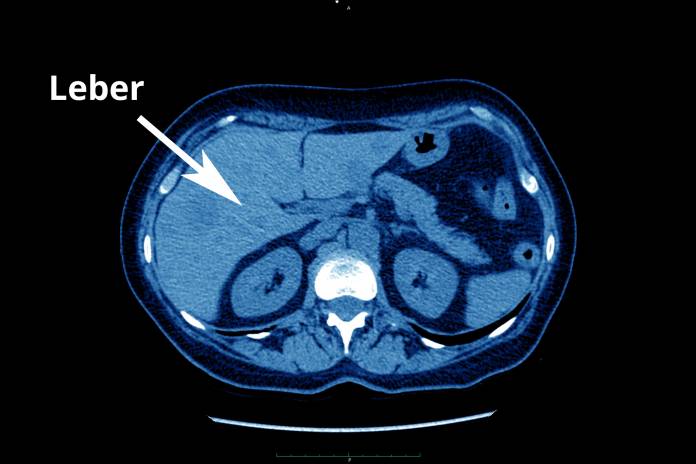

Patienten mit bösartigen Tumoren werden im Rahmen ihrer Therapie regelmäßig untersucht und nachuntersucht, z. B. durch bildgebende Verfahren. Besteht der Verdacht auf das Vorliegen von Lebermetastasen, können gezielte Untersuchungen ratsam sein. Dazu gehören: